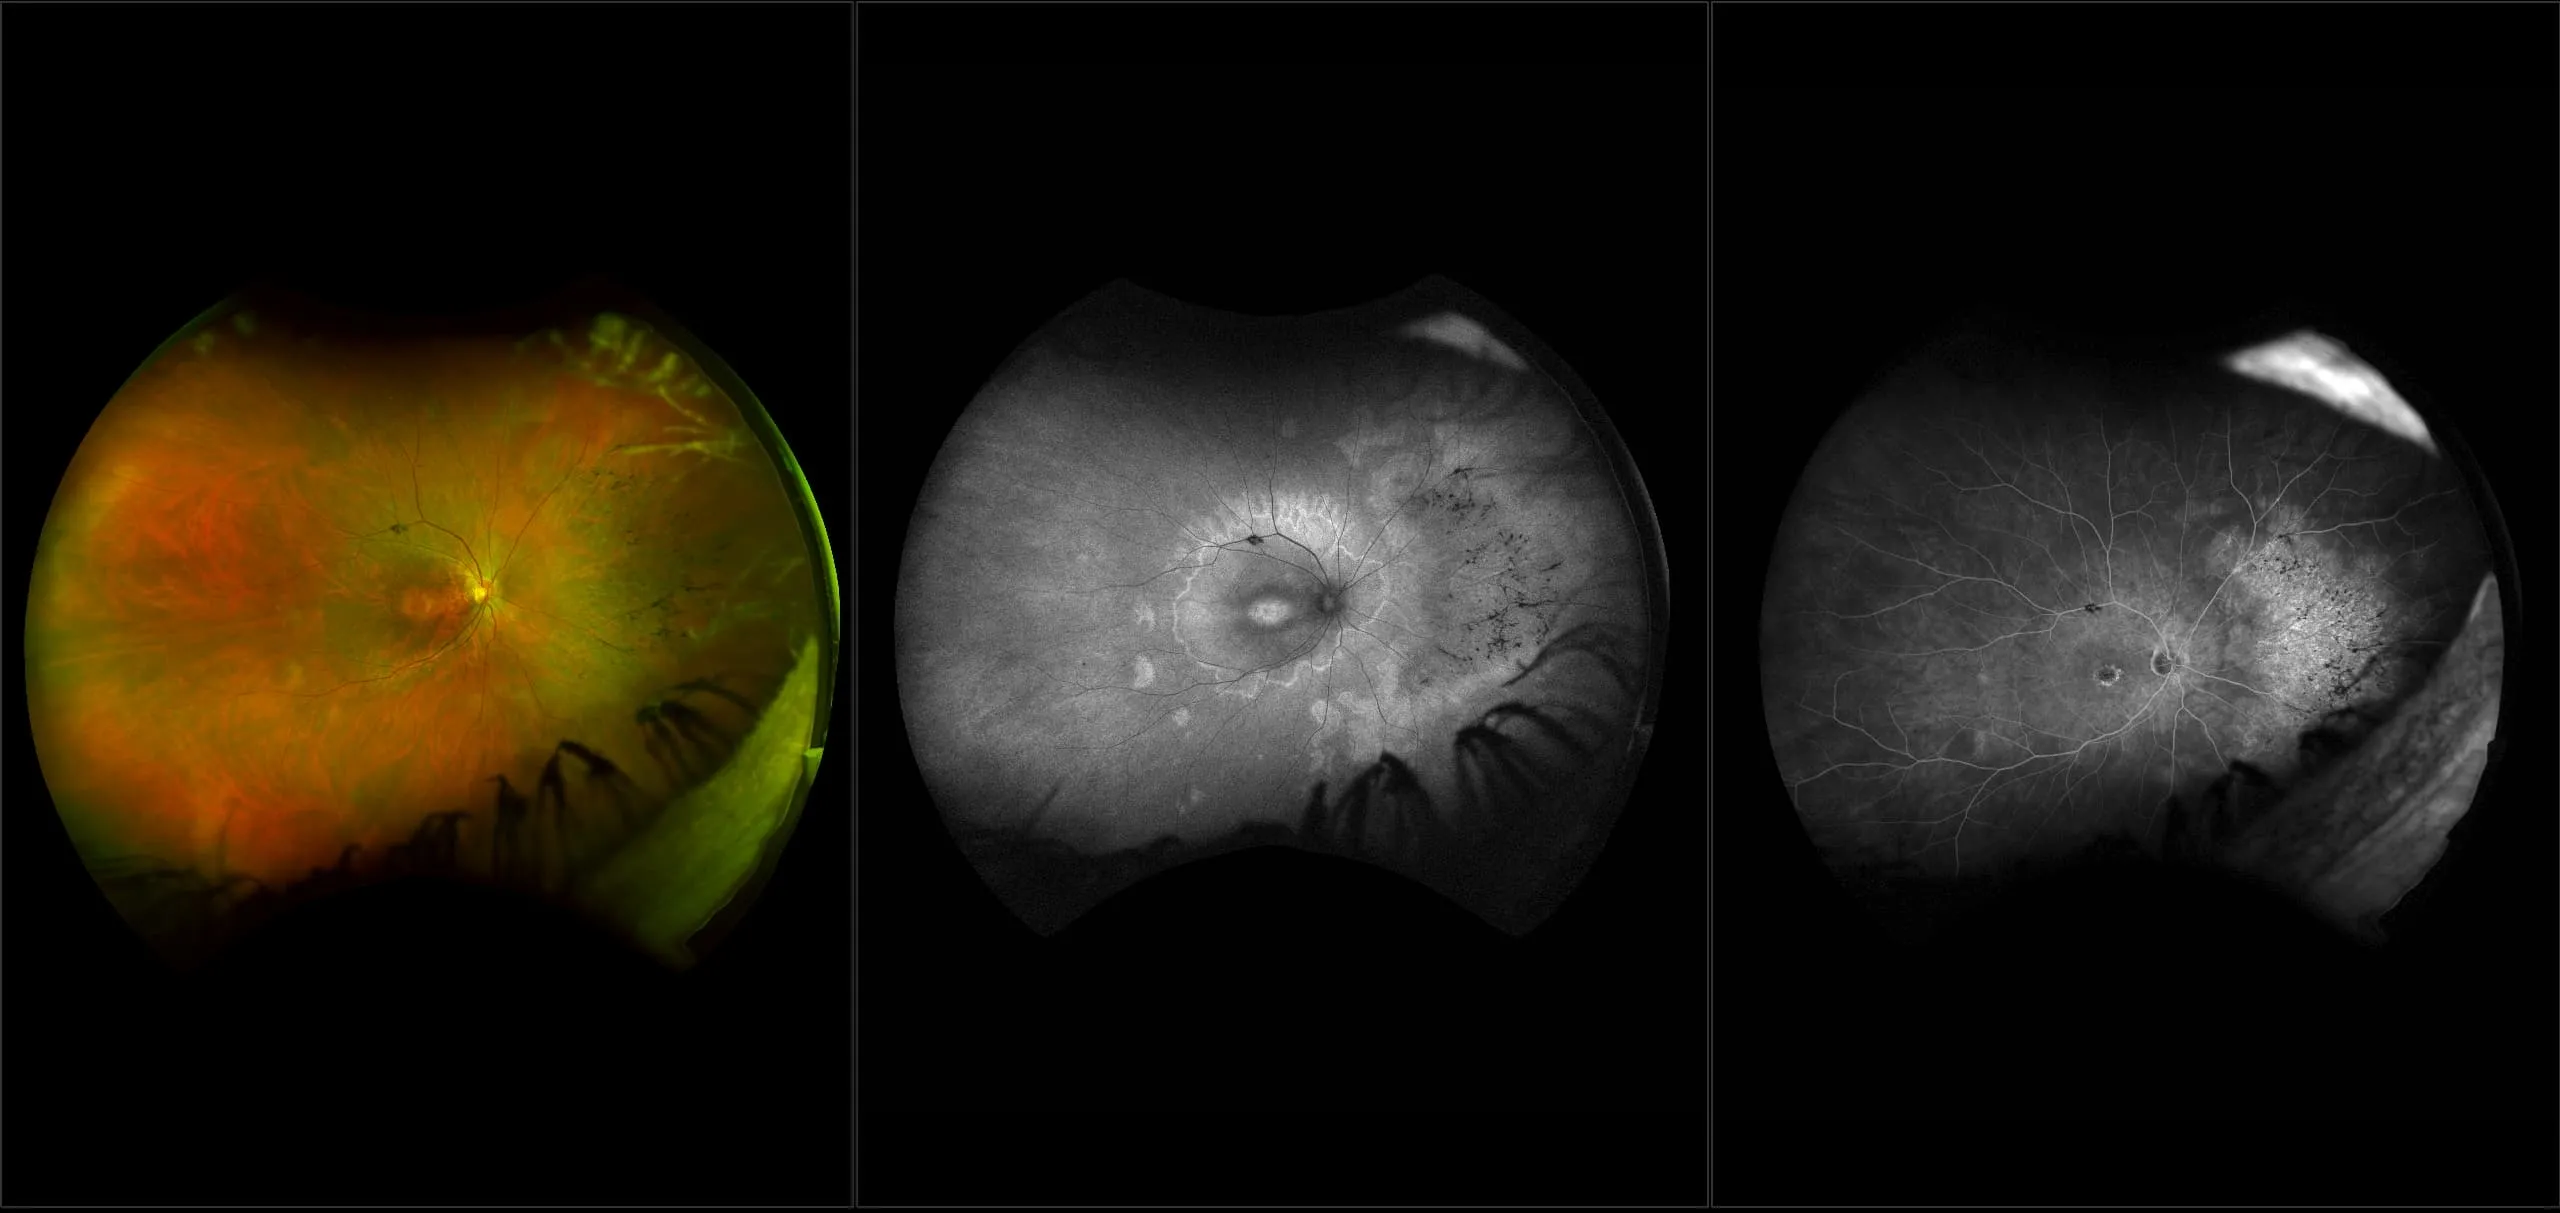

optomap® Recognizing Pathology

This material is designed as a searchable reference resource to support clinical decision-making. The information contained here should be used as general guidance when viewing optomap and OCT images from Optos devices. The differential diagnosis should be made under the direction of the responsible physician. These images were taken on the latest ultra-widefield optomap devices.

The Cases and Images

optomap Recognizing Pathology is searchable by pathology and/or optomap image modality. You may search by multiples of each selection. Each individual case is represented by the accompanying thumbnail image. Most cases include several different optomap image modalities. To view a full description of the case, please click on the thumbnail. Each image in the case will be made available through our OptosAdvance software which provides multi-dimensional visualization of digital images to aid in the analysis of anatomy and pathology. Support and pathology definitions can be found by selecting one of the buttons, above. Should you have questions, please complete the form below.